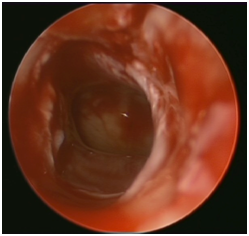

In this technique, the surgeon introduces a 2.9mm endoscope through the nasal cavity. Identification of choanal atresia is then performed. Using a straight suction, a puncture is performed anterior-inferiorly close to the vomer bone of the nasal septum (Figure 2A). Visualization of adenoid pad in the nasopharynx assures proper puncture through atresic palte and not into soft palate (false passage). The opening is then enlarged using a drill or shaver depending on the thickness of the atretic plate (Figure 2B, Figure 2C). A mucosal flap is usually not possible to preserve by the end of the procedure. The other choana atresia side is addressed similarly. Lastly, the vomer is removed using a backbiter forceps. Two size 3.5 endotracheal tubes are used one in each side and tied together anteriorly using a sub-labial suture for fixation to avoid collumellar pressure. The stent are removed in the clinic six weeks later.

A                                                                      B                                                            C

Figure 2 A) Transnasal endoscopic puncture using a straight suction for right choanal atresia. B) Shaver blade enlarging the puncture opening. C) Final result.